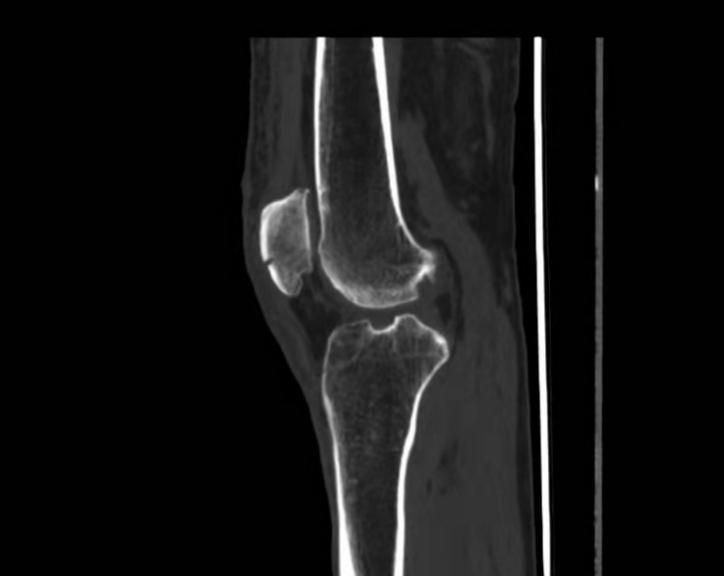

患者入院后,基于“右髌骨骨折”的考虑,进一步完善CT检查,心电图检查,超敏C反应蛋白测定,电解质测定,血常规,血凝以及血型检测,肝功和肾功等相关检查。这些检查的目的是为后续行手术治疗做准备。检查结果示患者右髌骨轻度骨折,髌上囊可见积液;窦性心律正常范围;超敏C反应蛋白增多,60.98mg/L,白细胞及中性粒细胞增多,血凝D二聚体2.11微克每升,总胆红素增多,直接胆红素增多。

基于上述检查结果,考虑患者右髌骨骨折,伴感染,结合患者具体疾病发生情况,可以临床诊断为右髌骨骨折,遂予以患者手术治疗,全麻双下肢清创缝合术,时长2~3小时。给予头孢类抗菌药及克拉霉素进行抗炎消菌,避免手术后感染,对皮肤破损及挫伤处用碘伏消毒,并涂抹抗炎乳膏,保持皮肤破损处清洁干燥。手术后给予患者补液治疗,维持身体稳态和手术后的身体虚弱。